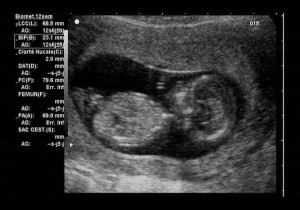

عن طريق الموجات فوق الصوتية ورصد وتصوير حركات الجنين، قام العلماء بتجارب من خلالها تم تعريض الجنين لأصوات عالية وحادة وتم قياس استجابة الجنين بانعكاس تم قياسه. ولذلك تأكد للعلماء أن الجنين يسمع جيدًا وبالذات في أواخر شهور الحمل بل وهو يعرف الأصوات المحيطة به ومن ضمن هذه الأصوات أصوات سريان الدم في المشيمة حوله.